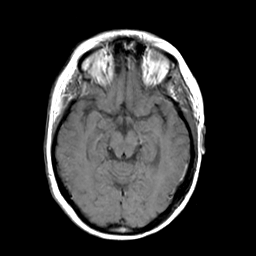

MR Study #3 -- Slice #23

[Home][Help][Clinical][Tour 1][Tour 2][Tour 3] Slice 23